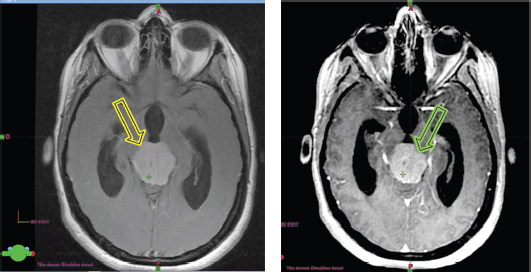

Upon her admission to the neurosurgery department at our institution, a brain MRI (Figure 2a and b) was performed, revealing an extra-axial supratentorial tissue mass centered on the pineal gland. The mass was roughly round in shape, well-defined, with lobulated contours, described as isointense on T1, T2 and FLAIR sequences compared to the gray matter. It contained a central area of hyperintense signal on T2, with restricted diffusion on diffusion-weighted imaging, and showed moderate and heterogeneous contrast enhancement after the injection of contrast agent, containing some vascular structures. No calcifications or hemosiderin deposits were observed on T2*. Spectroscopy revealed a peak of choline and a drop in N-acetyl-aspartate (NAA) (Choline/NAA ratio > 2). The mass measured 28 × 32 × 30 mm in diameter (APxTxH) and extended anteriorly, displacing the fourth ventricle, leading to bi-ventricular dilation (with measurements of 23 mm on the right and 26 mm on the left), showing signs of transependymal resorption. Inferiorly and posteriorly, it exerted pressure on the superior vermis, with a persistent layer of cerebrospinal fluid (CSF) separating it, and superiorly, it encompassed the two internal cerebral veins, which remained patent. The MRI also showed signs of increased intracranial pressure, characterised by flattening of the posterior poles of the eyeballs, thickening of the optic nerve sheaths and an arachnoidocele.

Figure 2. (a): The isointense tumour lesion in T2 flair. (b): Hyperintense in T1 Gado.